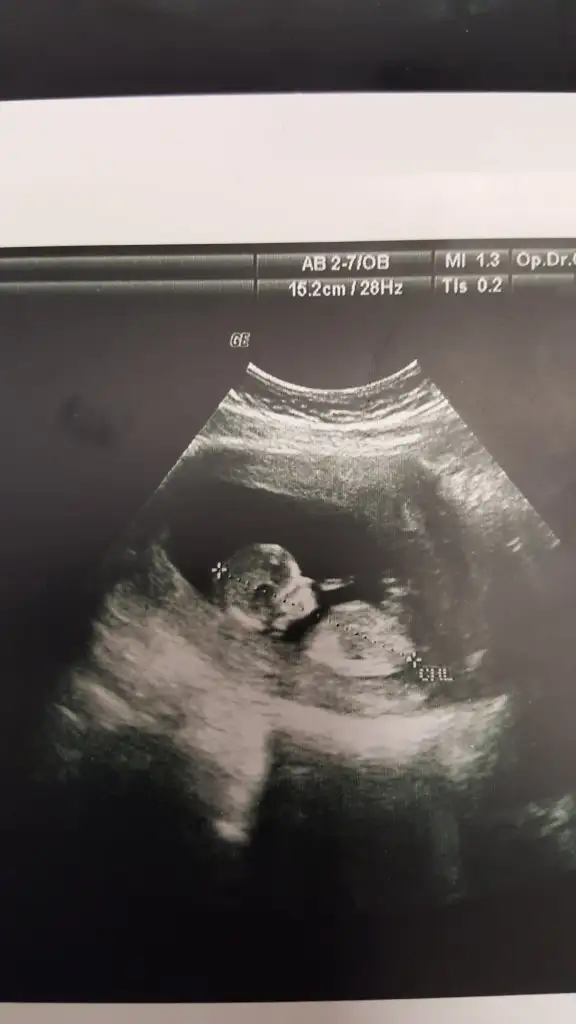

Karından bakıldı ise kız en iyi nub için 11 12 13 hafta paylaşınIkra meyra canım bakar mısın ilk fotoyu atmıstım daha önce ikinci foto 7. Haftadan

Canım ilk foto için karındansa erkek demiştin bende 7. Hafta fotosunu atayım dedim 10. Haftamda tekrar gideceğim o zaman yine atayımKarından bakıldı ise kız en iyi nub için 11 12 13 hafta paylaşın

Evet biliyorum ilkte erkrek demiştim kese konumu pek guven vermiyor o nedenle 11 12 13 hafta usg olursa paylalın 10 haftada değilde 11 haftada gitsenizCanım ilk foto için karındansa erkek demiştin bende 7. Hafta fotosunu atayım dedim 10. Haftamda tekrar gideceğim o zaman yine atayım

Hem net değil hemde 11 12 13 hafta olmalıBana da tahmin yapabilir misiniz 15+1 göstermedi cinsiyeti bugün bıcırık :)Ikra meyra

Mrb 13 haftalik olduk cok sukurKız gibi net de değil kız sanki 12-13 olunca tekrar usg paylaşın

bu da diger acidan fotografi ayagi kapatmis gibi amabu bu haftaki goruntusu 12. hafta gecen hafta erkek demistiniz ama emin olamamistiniz@ikrameyra